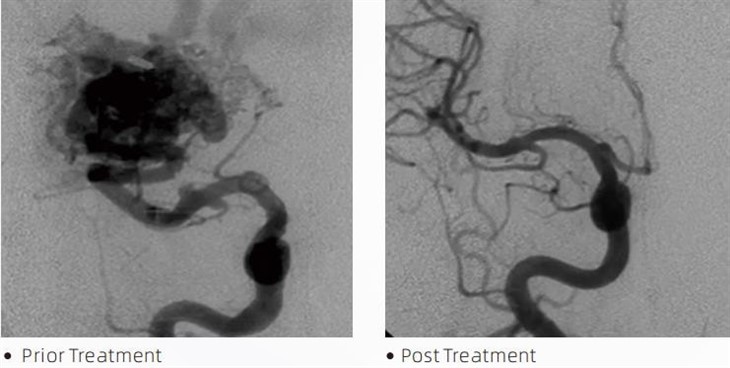

LavaTMembolic lim är en medicinsk anordning som används av interventionella neuroradiologer under minimalt invasiva procedurer för att behandla tillstånd som cerebrala aneurysmer, arteriovenösa missbildningar och tumörer. Lava-embolilimmet erbjuder flera fördelar för både medicinsk personal och patienter när det gäller säkerhet, användarvänlighet och effektivitet. Lava kan täta blodkärl snabbt och effektivt. Processen går ut på att injicera limet direkt i det riktade kärlet, där det polymeriserar och hårdnar till en gjutformig massa som fyller aneurysmen eller missbildningen. Då stänger det effektivt av blodflödet till lesionen, förhindrar att det brister och minskar risken för permanent skada eller stroke. Lava inkluderar Lava-12, Lava-18 och Lava-34. Varje formulering är utformad för att möta specifika kliniska behov. Lava-18 är standardformulering för allmänt bruk. Lava-34 är högvisköst lim för högflödeskärl. Medan Lava-12 har en lägre viskositet och är mer flytande, vilket möjliggör distala mikrokärl. Med dessa alternativ kan interventionella neuroradiologer välja lämpliga Lava-formuleringar för att säkerställa optimala resultat. En av de mest anmärkningsvärda egenskaperna hos Lava är dess icke-vidhäftande egenskaper. Detta ämne är speciellt framtaget för att förbli stabilt tills det når målområdet. Denna egenskap innebär att Lava-embolilim kan placeras exakt i artären och förbli där utan att klibba eller binda till den omgivande vävnaden.